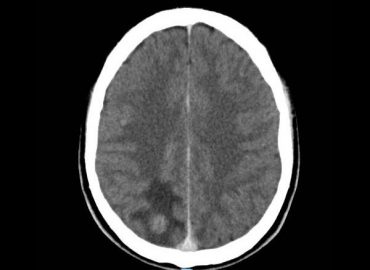

Femenino, 71 años. Sospecha de ACV agudo.